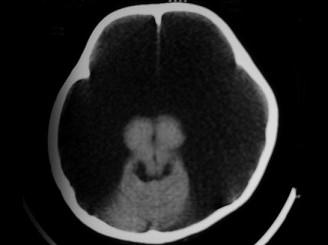

问题 女,1岁半,头颅迅速增大,行CT检查如图,请选出最可能的诊断 ( )

选项 A、硬膜下积液 B、脑内血肿 C、硬膜外血肿 D、硬膜下血肿 E、积水型无脑畸形

答案 E